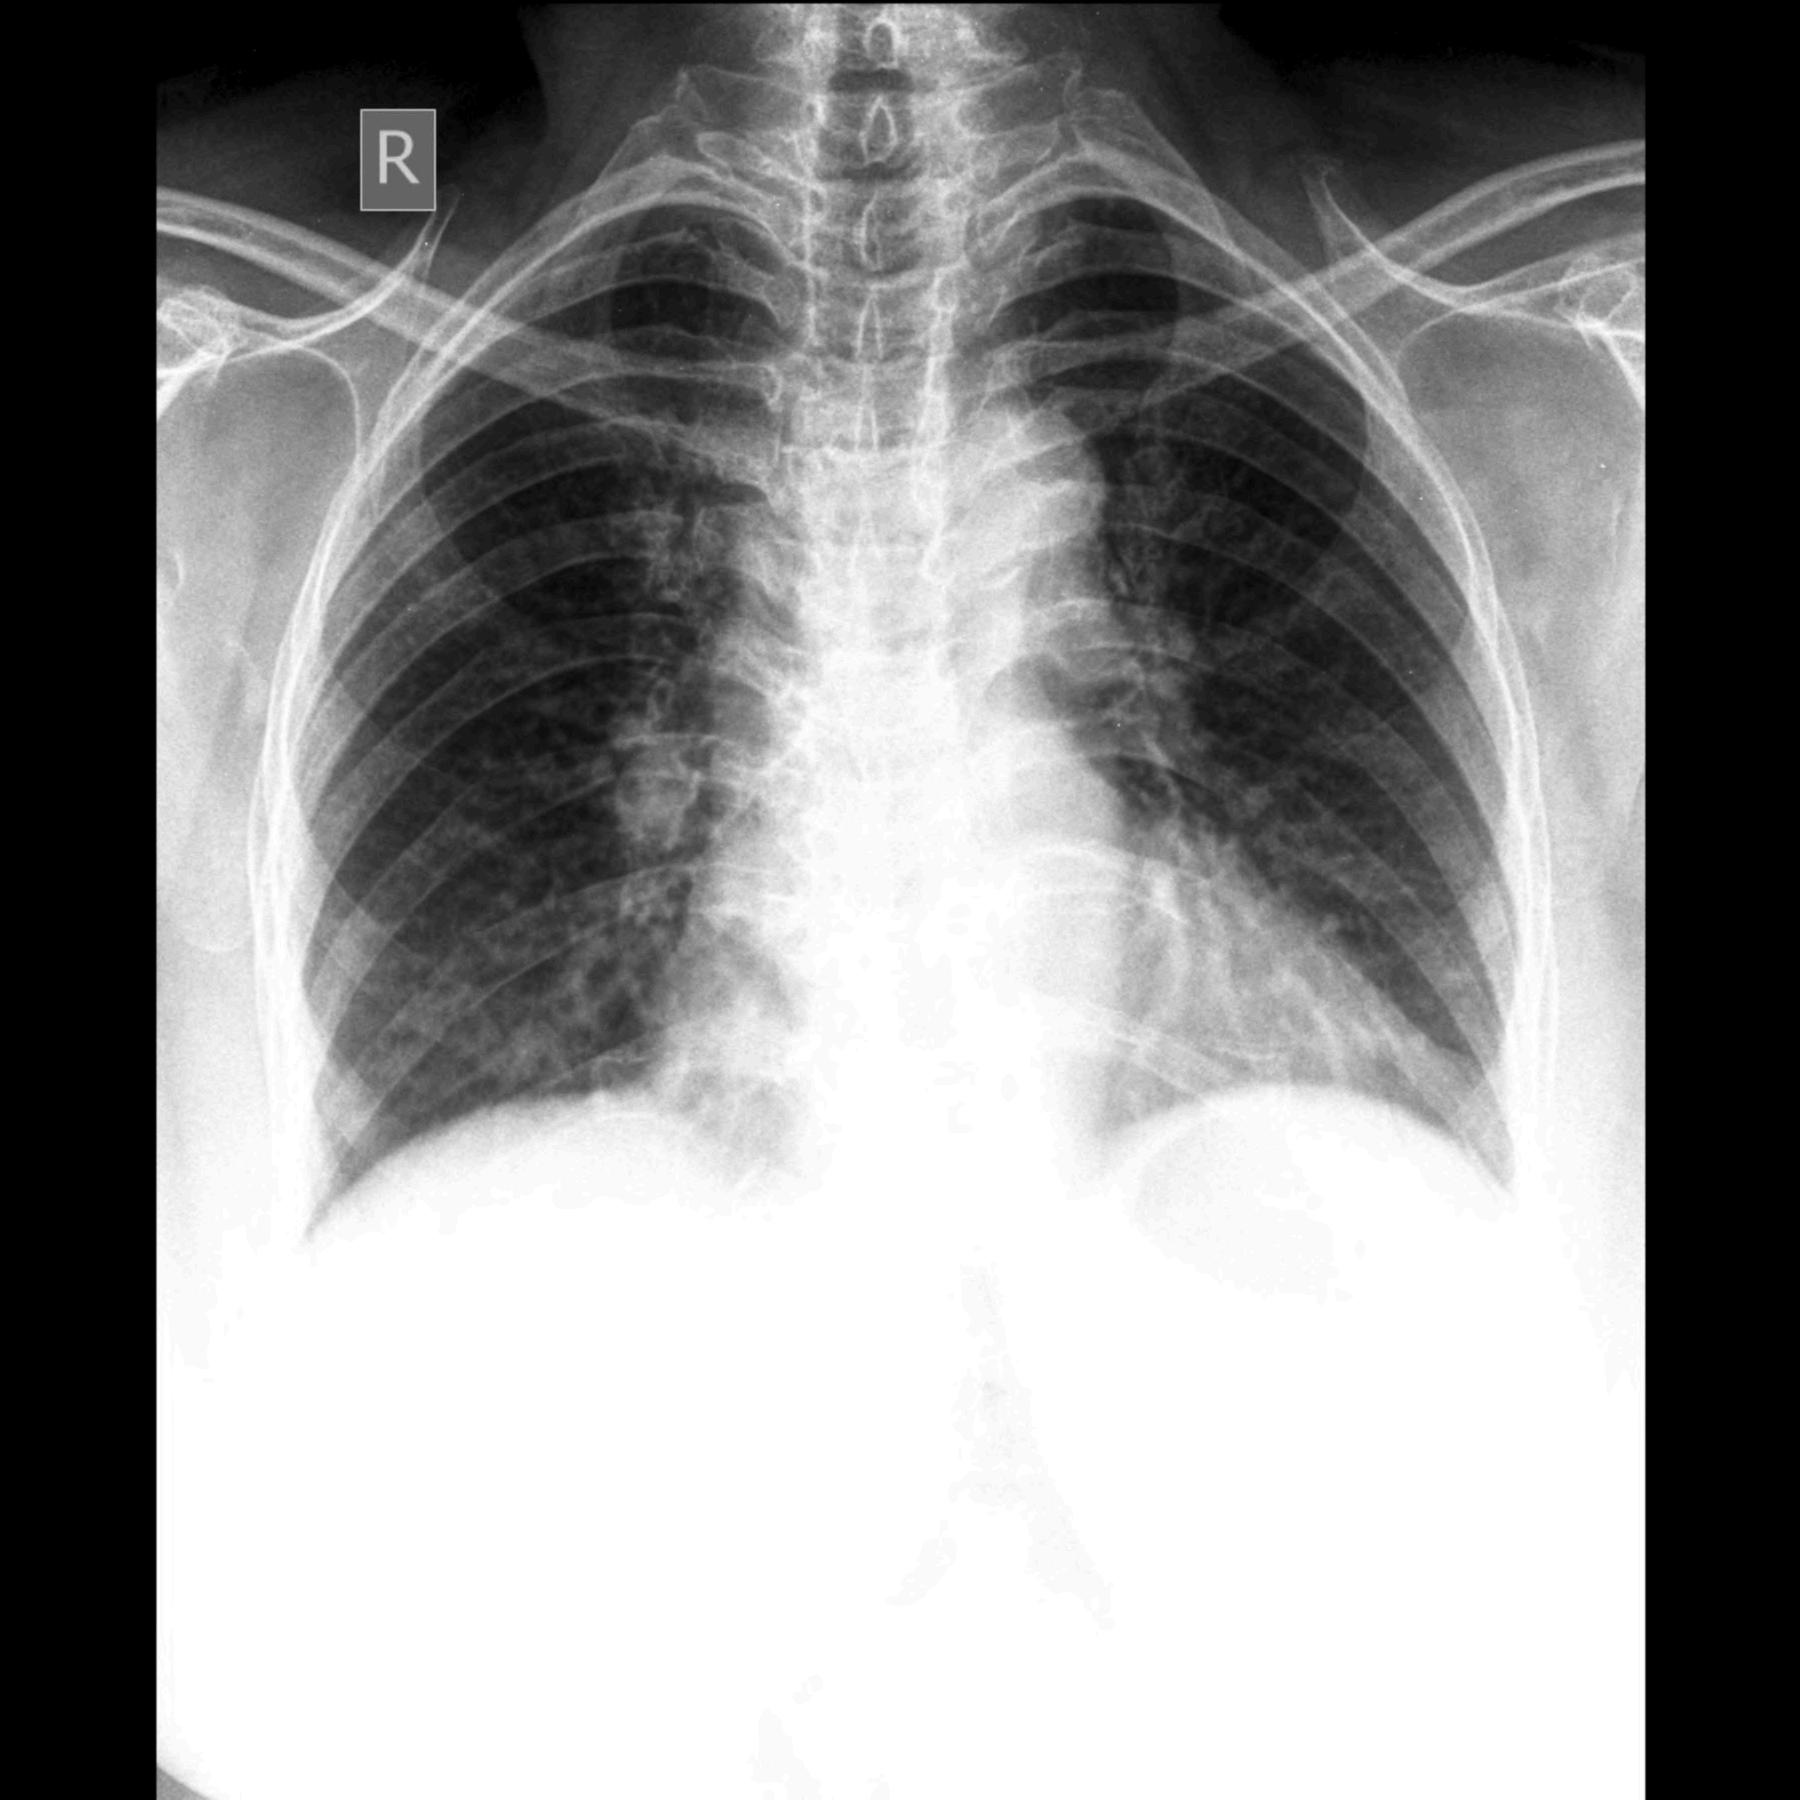

Cada 24 de marzo el mundo recuerda una de las enfermedades más antiguas y persistentes que ha enfrentado la humanidad: la tuberculosis La fecha no es casual Ese día, en 1882, el médico alemán Robert Koch anunció el descubrimiento del bacilo responsable de la enfermedad, un hallazgo que transformó la comprensión de una dolencia que durante siglos había sido un misterio mortal.

Hoy, más de 140 años después de aquel descubrimiento, la tuberculosis sigue siendo uno de los mayores desafíos de salud pública del planeta. Aunque existen tratamientos eficaces, la enfermedad continúa afectando a millones de personas cada año y provoca más de un millón de muertes en el mundo, lo que la convierte en una de las infecciones más letales conocidas

La tuberculosis es causada por una bacteria llamada Mycobacterium tuberculosis, que se transmite principalmente por el aire cuando una persona enferma tose, habla o estornuda Aunque puede afectar a diferentes órganos del cuerpo, su forma más común es la pulmonar Los síntomas incluyen tos persistente, fiebre, sudoración nocturna, fatiga y pérdida de peso Sin embargo, más allá de su impacto sanitario actual, la tuberculosis es también una enfermedad profundamente ligada a la historia humana